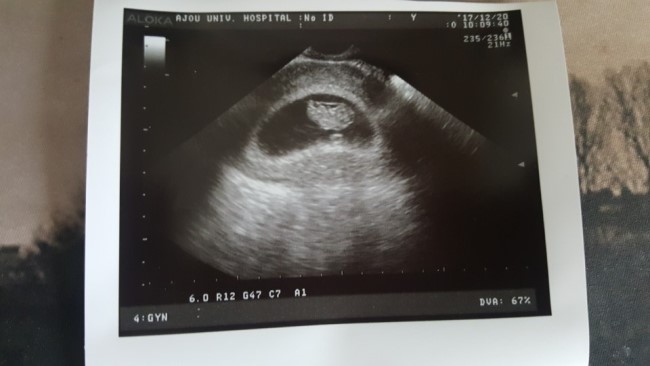

세번째 만남

2017. 12. 20 (+ 9주1일) 만복이 잘 있는지 2주만에 보러갔던 9주1일 첨엔 보이지도 않았고 두번째는 째깐...